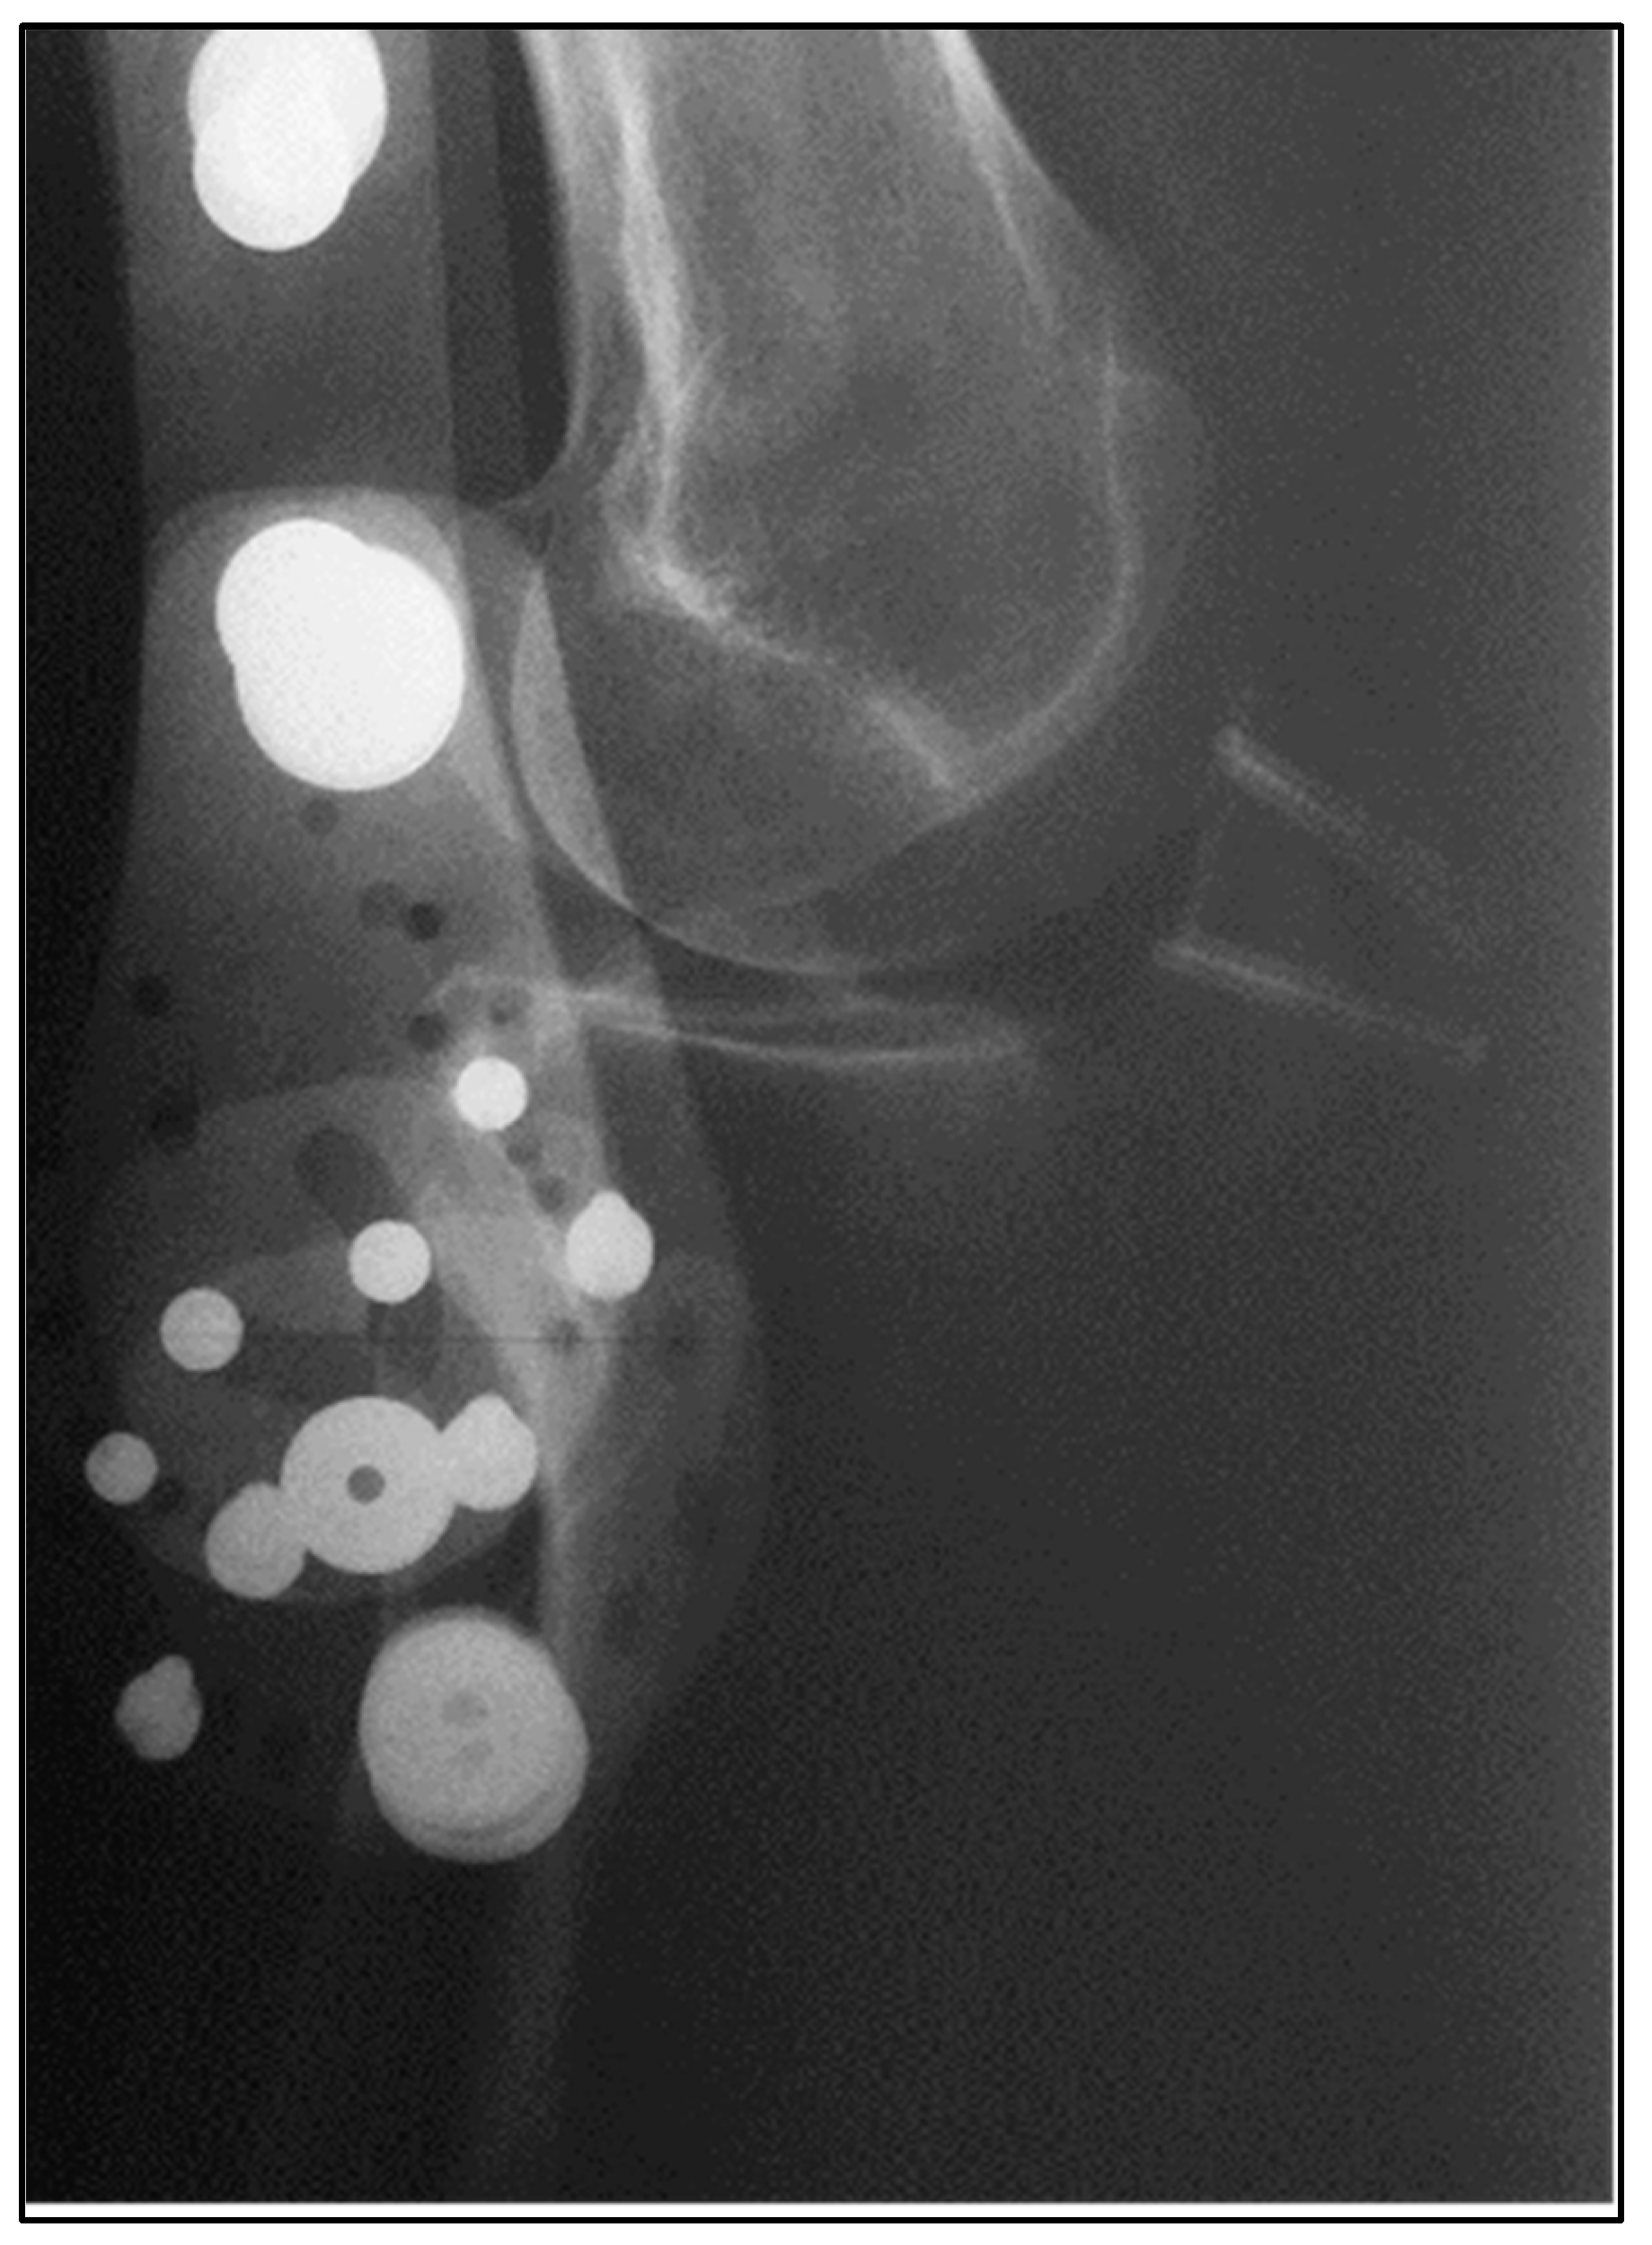

| Graft Signal Intensity | Mildly increased on T2 | Mildly increased on T2 |

| Fiber Continuity | Continuous alignment, minor edema | Continuous alignment, minor edema |

| Bone Block Integration | Early bridging at the patella | Early bridging at the calcaneus |

| Hardware Artifact | Minimal, no screw loosening | Minimal, no screw loosening |

| Signs of Complication | None | None |